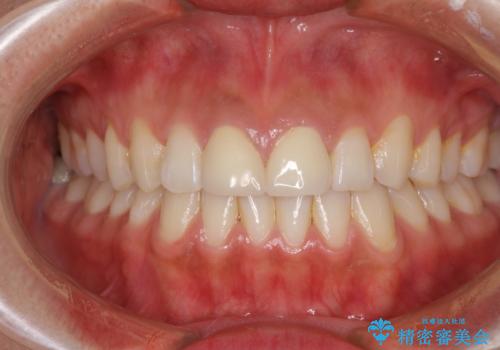

前歯の隙間をオールセラミックで閉じる

虫歯もない前歯を削ることは、処置をする者として心苦しいのですが、患者様は矯正治療は選択しないとのことだったので、オールセラミッククラウンにて補綴治療を行いました。

短期間で思い通りの仕上がりとなり、患者様には大変満足していただきました。